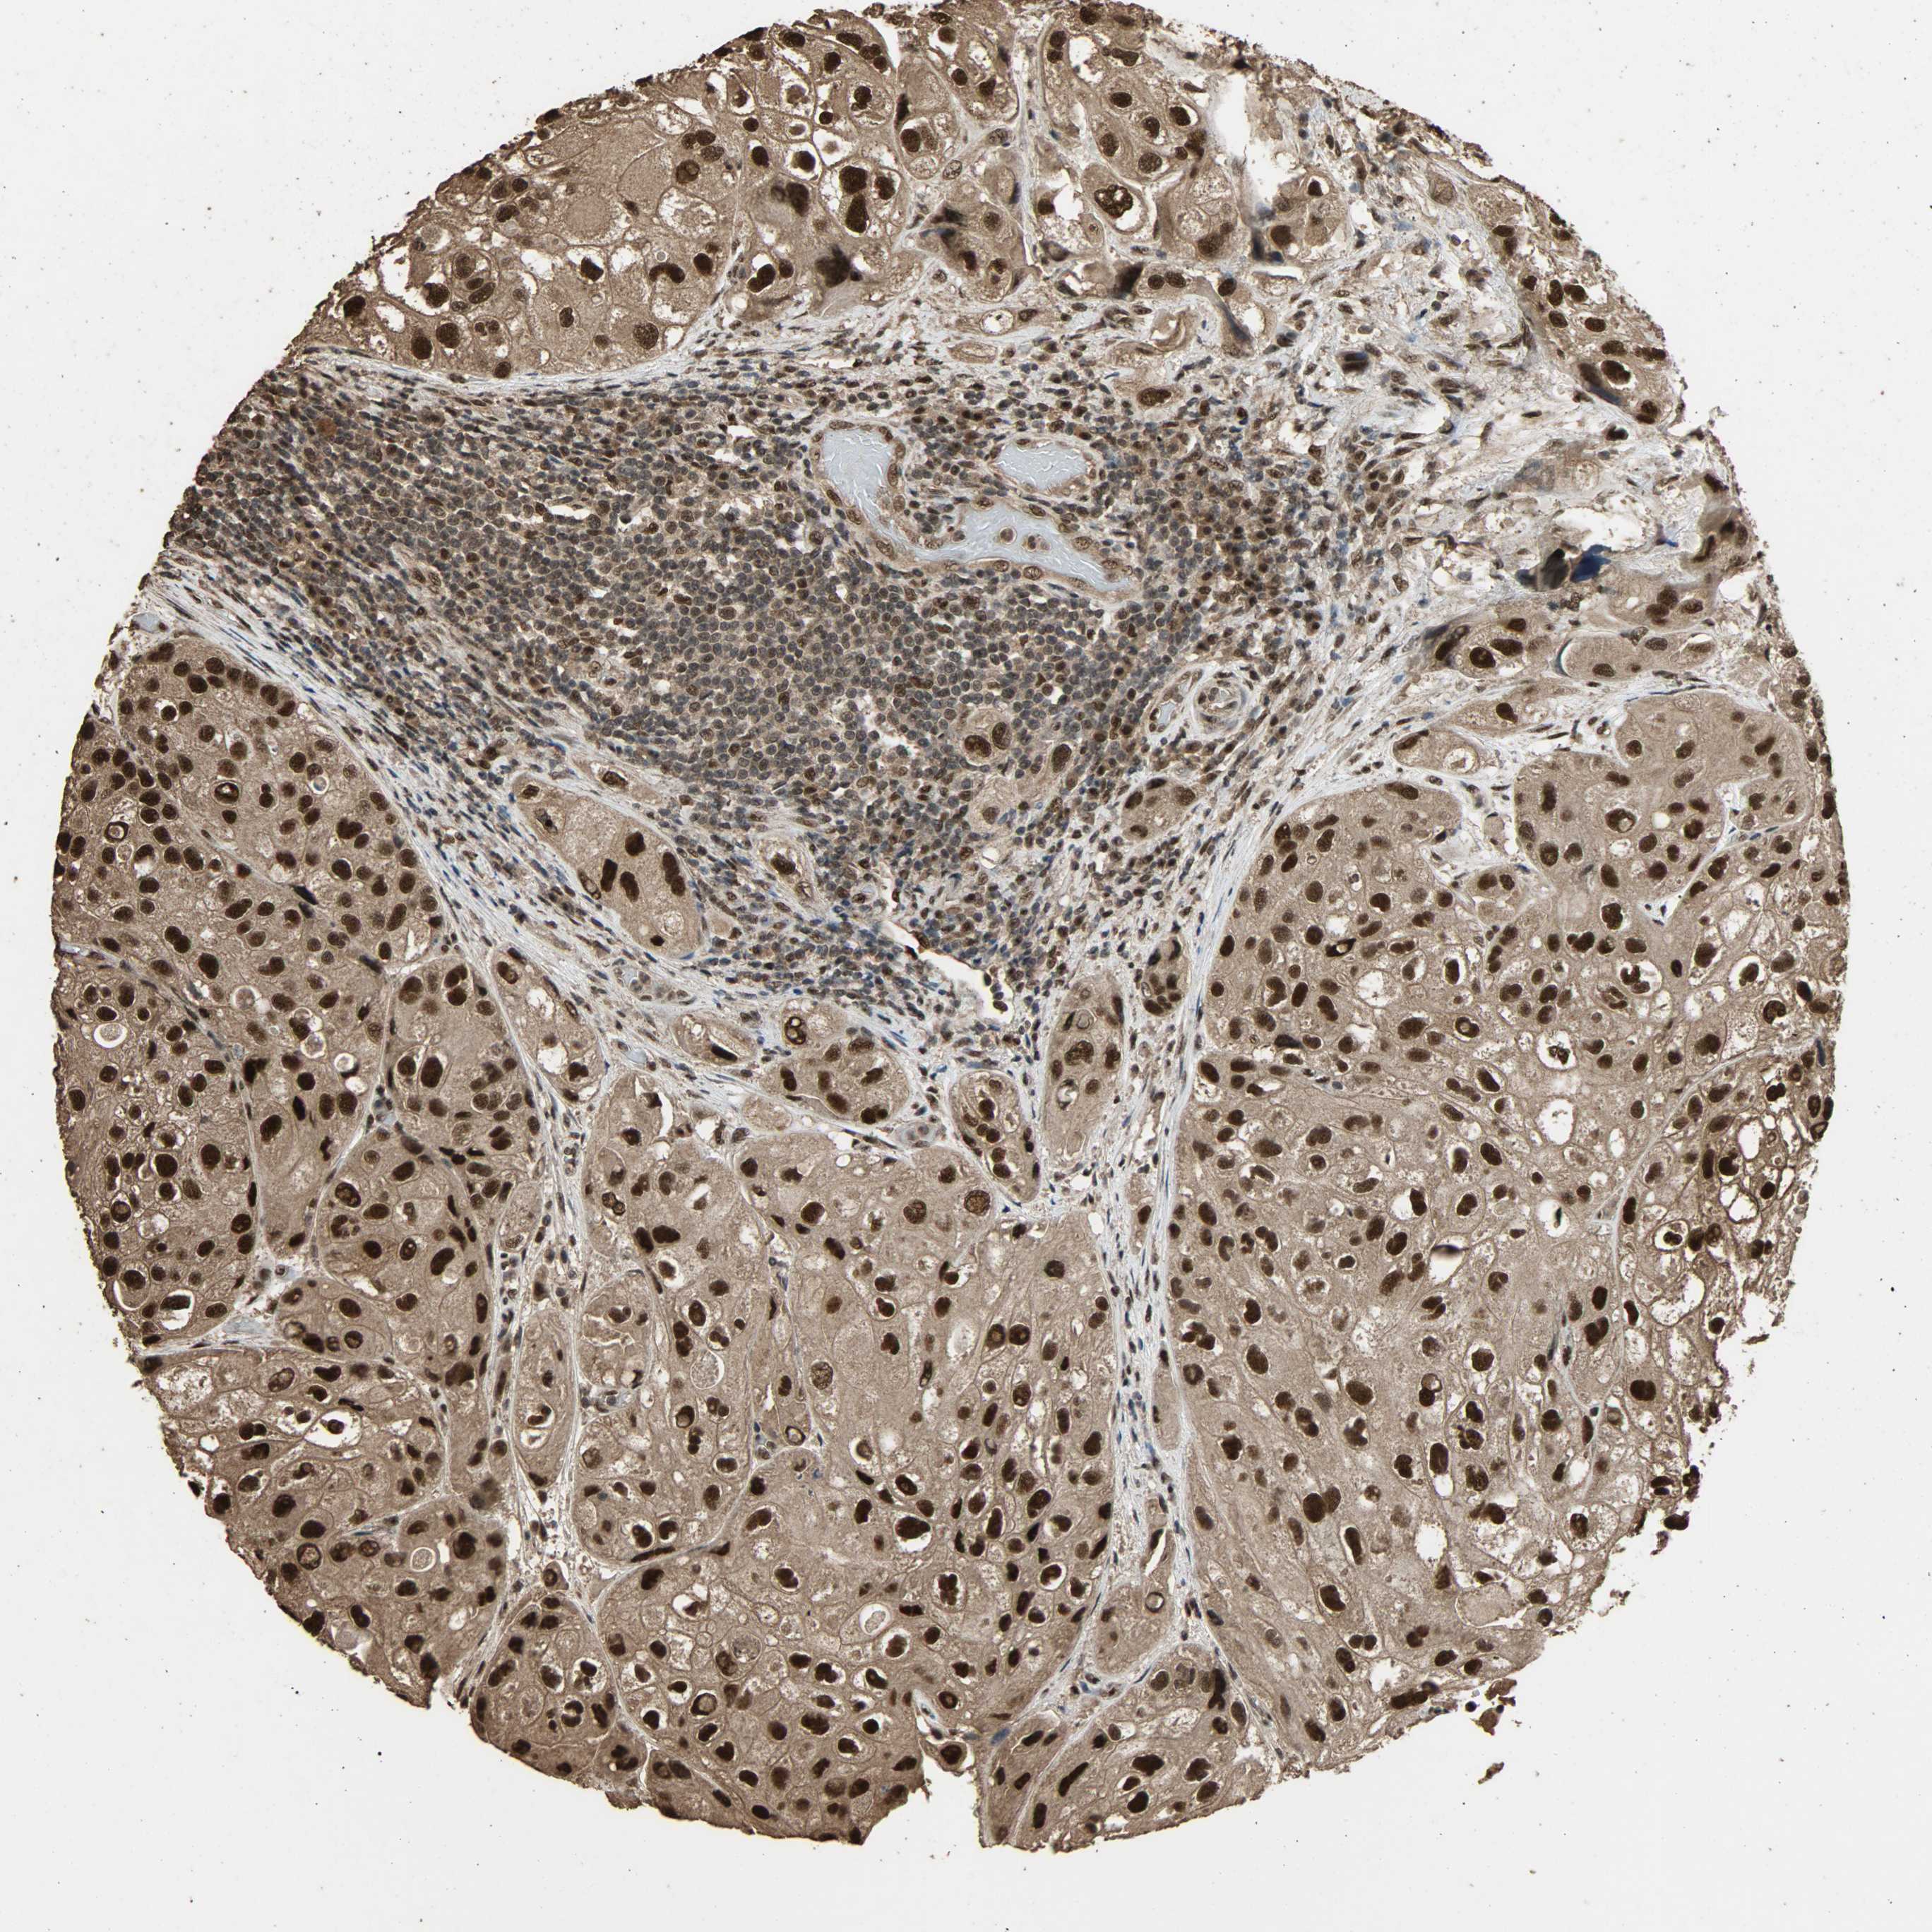

UROTHELIAL CANCER - Protein expressioni

A mouse-over function shows sample information and annotation data. Click on an image to view it in a full screen mode. Samples can be filtered based on level of antibody staining by selecting one or several of the following categories: high, medium, low and not detected. The assay and annotation is described here.

Note that samples used for immunohistochemistry by the Human Protein Atlas do not correspond to samples in the TCGA dataset.

Antibody stainingi

Antibody staining in the annotated cell types in the current human tissue is reported as not detected, low, medium, or high, based on conventional immunohistochemistry profiling in selected tissues. This score is based on the combination of the staining intensity and fraction of stained cells.

Each image is clickable and will lead to virtual microscopy that enables deeper exploration of all samples and also displays staining intensity scores, fraction scores and subcellular localization as well as patient and tissue information for each sample.

Antibody HPA005559

Staining

High

Medium

Low

Not detected

Intensity

Strong

Moderate

Weak

Negative

Quantity

>75%

75%-25%

<25%

None

Location

Nuclear

Cytoplasmic/membranous

Cytoplasmic/membranous,nuclear

Urothelial carcinoma, High grade

Urothelial carcinoma, Low grade